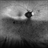

- A 60-year-old Caucasian female presented with reduced night vision and constricted visual fields. The fundus exam revealed pigmentary changes in the peripheral retina. Fundus autofluorescence depicted the schematic appearance of a Phoenix , with the hypo-autofluorescence corresponding to the head and wings of the phoenix. Genetic testing was positive for a heterozygous RHO mutation